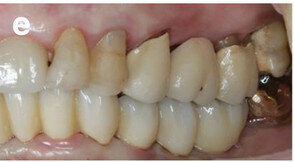

Figs. 2a & b: Initial dental status: right side (a) and left side (b).

The dental status showed acceptable oral hygiene and some teeth with Grade III mobility (teeth #41, 31, 32, 18 and 28) and local periodontal problems, including horizontal bone loss (teeth #42, 41, 31, 32, 33, 18, 17, 27 and 28). Teeth #42 and 33 were healthy and not mobile. The alveolar crest in the lateral mandible area showed clinically a wide shape with thick keratinised mucosa. The initial panoramic radiograph revealed stable crestal bone in the lateral mandibular area (Figs. 1–3). Thus, in the lower jaw, the single-tooth prognosis was fair for teeth #47, 42 and 33, and hopeless for teeth #41, 31 and 32.[24]